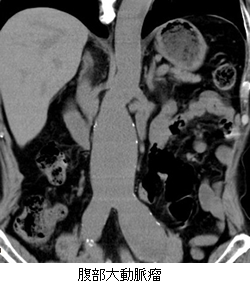

腹部CT

腹部に重点を置いたCT検査になります。

メタボ(皮下脂肪や内臓脂肪)の状態や腹部大動脈瘤、腎臓や肝臓等の疾患を診断することが可能です。